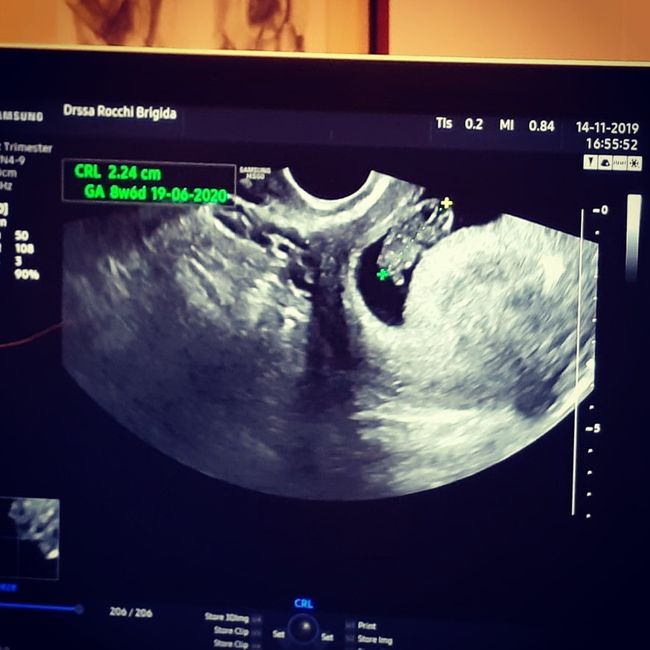

Ragazze finalmente mi sono tranquillizzata!;Ieri ho fatto la seconda eco ed è andata benissimo, il fagiolino è cresciuto un sacco, in 16 giorni è passato da 6mm a 2.24 cm ahahahah ed oggi entro ufficialmente nel terzo mese!!!La dottoressa mi ha detto che si muove un sacco eheheheh in effetti durante la visita un po' si vedeva di spalle e un po' di profilo!!Sono già follemente innamorata Smiley heart